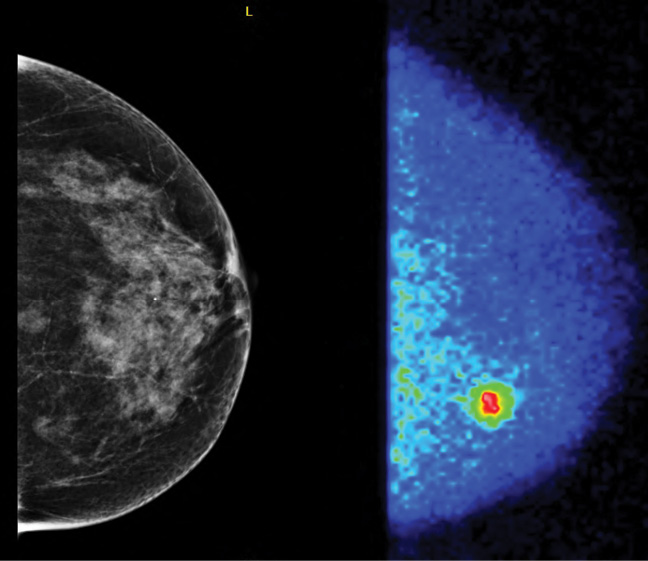

In the side-by-side comparison (See top right, Page 12), the screening mammogram was interpreted as negative; however, the MBI study clearly showed an area of focal uptake in a region where the breast tissue was dense. This corresponded to an 11 mm invasive ductal carcinoma.

"Breast tumors very avidly take up sestamibi," said Dr. O'Connor, who collaborated on the research with radiologists, surgeons and physicians at the Breast Diagnostic Clinic at Mayo Clinic in Minnesota. "With this technique, we're not looking at the architecture of the lesion, but rather its metabolic activity."

The women in the study underwent mammography and MBI, a relatively new breast imaging technique pioneered by Michael O'Connor, Ph.D., a professor of medical physics in Mayo's Department of Radiology. MBI utilizes a small gamma camera to acquire images of the breast after injection of the radiotracer sestamibi.